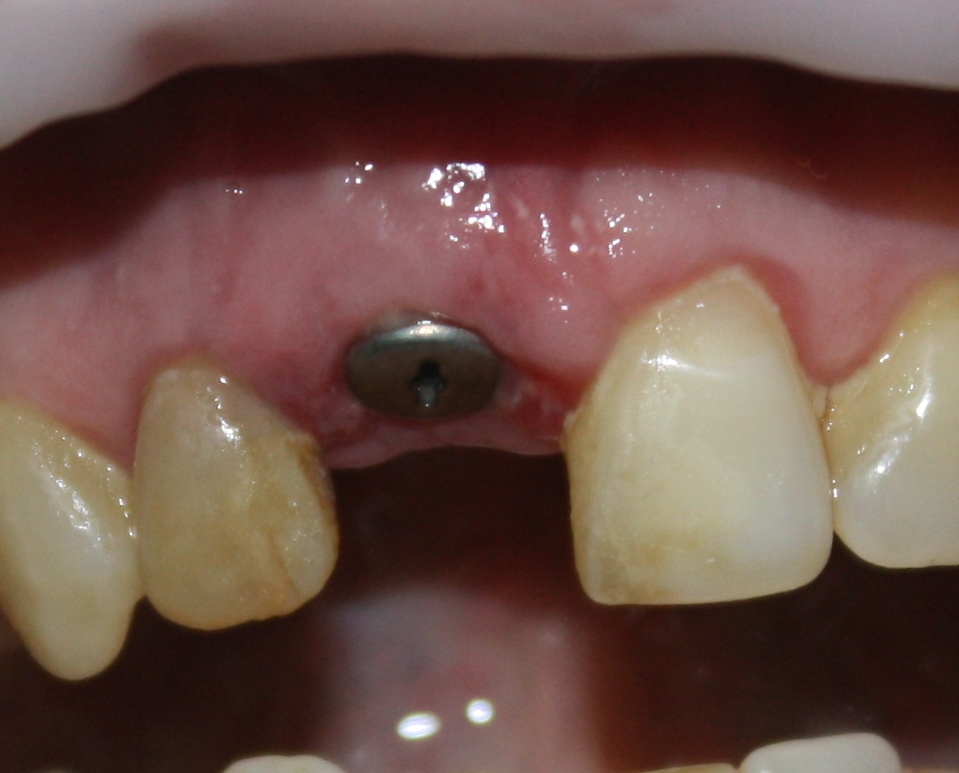

Немедленная имплантация — оптимальное решение в любой клинической ситуации